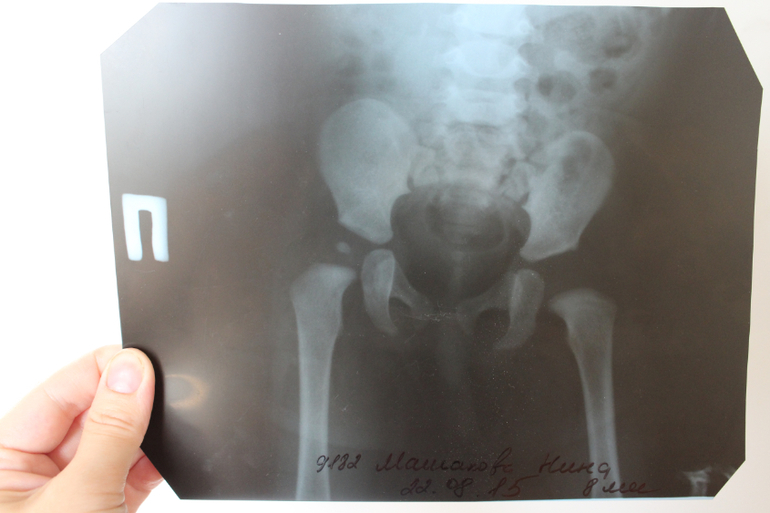

Рентген ТБС: Нормальные показатели

Раздел: Необычные решения